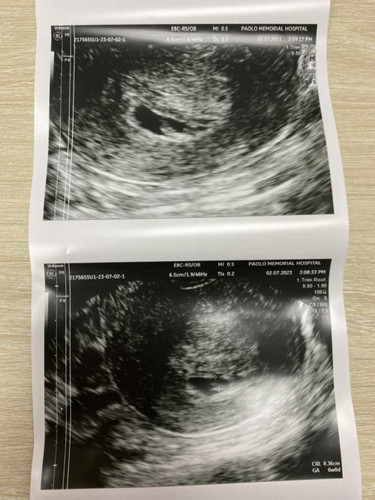

ภาวะแท้งคุกคาม ตอนนี้ตั้งครรภ์ได้8วีคแต่ ซาวด์ครั้งแรกหมอบอกว่าน้องแค่6วีคเอง มีเลือดออกเหมือนตอนเป็นประจำเดือนปวดท้อง

เรามีอาการแท้งคุกคามตอน สัปดาห์ที่6ค่ะ นั่งอยู่ดีๆรู้สึกมีอะไรหล่นออกมาจากช่องคลอดเลยเข้าห้องน้ำดู เป็นลิ่มเลือดก้อนประมาณ 5-6ซม.ค่ะ ตกใจและกังวลมาก แต่ออกมาแค่นั้นนะคะ เลยรีบนอนราบนิ่งๆไว้ตลอด เช้าวันถัดมารีบไปหาหมอมีนัดพอดี ทำใจไว้แล้ว นอนไม่หลับทั้งคืนเลยค่ะ สรุปว่าอัลตราซาวด์เจอหัวใจน้องเต้นค่ะ น้องยังอยู่ดีใจมากๆ คุณหมอให้กินยากันแท้งด่วนเลยและได้ยาสอดมาด้วยค่ะ เลือดออกแค่วันนั้นวันเดียวและไม่ทราบสาเหตุเหมือนกันค่ะ คุณหมอแนะนำให้นอนราบเยอะๆ อย่าเดินเยอะ อย่ายกของหนัก และกินยา สอดยากันแท้งไปจนครบ 12สัปดาห์ค่ะ ตอนนี้ 21สัปดาห์แล้ว เอาใจข่วยคุณแม่นะคะ แนะนำให้พักผ่อนเยอะๆนอนราบเยอะๆและอย่าเครียดช่วงนี้ค่ะ ปล.ก่อนที่ลิ่มเลือดจะออกมา เรามีไปปลูกต้นไม้ยกกระถางต้นไม้ออกแรงตักดิน และเพิ่งร้องไห้อย่างหนักจากการสูญเสียน้องหมา คิดว่ามีผลกระทบกับการตั้งครรภ์ค่ะ ยังไงปฏิบัติตามคำแนะนำของหมอไว้ดีที่สุดค่ะ และระมัดระวังตัวเองเป็นพิเศษด้วยค่ะ

Đọc thêmเรามีประวัติเคยแท้งค่ะ ท้องนี้หมอเลยฉีดยากันแท้งตั้งแต่ 6 สัปดาห์ + กินฮอโมนทุกวัน ส่วนยาฉีด สัปดาห์ละ 1 เข็ม เข้าสัปดาห์ที่ 8 มีเลือดออกสีน้ำตาล ตอนกลางคืน เช้ามารีบไปหาหมอ หมอให้หยุดงานนอนประมาณ 7 วัน ก็ดีขึ้นค่ะ เลือดหยุดในวันที่ 2 เลย แล้วก็ฉีดยากันแท้งจนถึงสัปดาห์ที่ 13 ซาวดูทุกรอบ ตอนนี้ 19 สัปดาห์แล้วน้องตอดเก่งมากค่ะ ก็ยังระวังตัวอยู่ตลอด ไม่เดินเยอะ ไม่ทำอะไรเร็วๆ คุณแม่ปฏิบัติตามหมอแนะนำนะคะ ไม่ต้องกังวล สู้ๆค่ะ